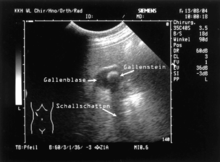

Zur apparativen Untersuchung der Gallenblase und der Gallenwege sowie eventueller krankhafter Erscheinungen steht eine Vielzahl von Verfahren zur Verfügung. Von diesen ist die Sonografie die verbreitetste, da sie einfach durchzuführen und für den Patienten risikofrei ist. Somit ist die Sonografie das erste Verfahren zur Beurteilung der Gallenblase, an das sich gegebenenfalls weitere Untersuchungen anschließen. Die Untersuchung wird üblicherweise am nüchternen Patienten durchgeführt, da dann die Gallenblase gefüllt und am besten zu beurteilen ist.[11]